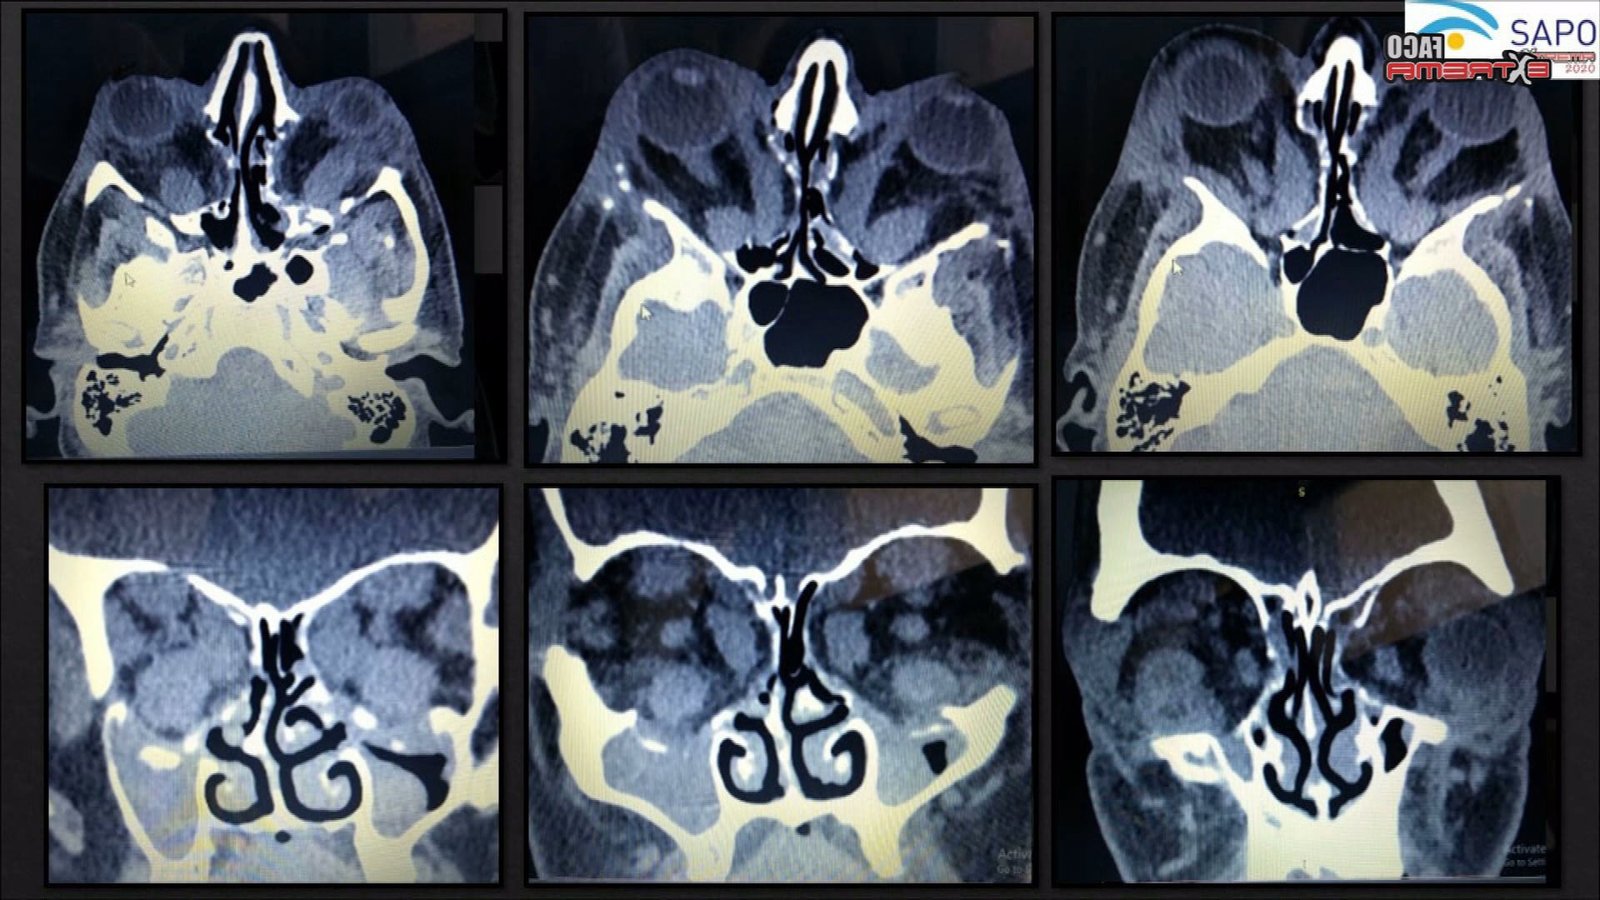

Trauma Extrema

Ximena Arze